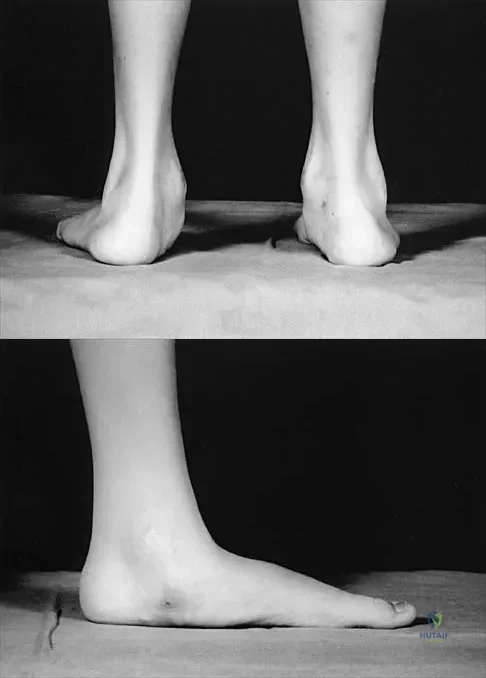

Figures 50a and 50b show the standing clinical photographs of a 12-year-old boy who has had increasing pain in the left foot for the past 9 months. He reports that the pain is activity related, aching in nature, and localized to the medial aspect of the midfoot and hindfoot. History reveals that he sustained a puncture wound located superior and posterior to the medial malleolus from a plate glass window 18 months ago. Examination reveals no restriction of ankle or subtalar motion, normal neurovascular status, no masses, and a well-healed 1.5-cm laceration posterior to the superior aspect of the medial malleolus. Inversion strength of the foot is decreased to grade 3/5. Radiographs of the foot show no bony abnormalities. Treatment should consist of